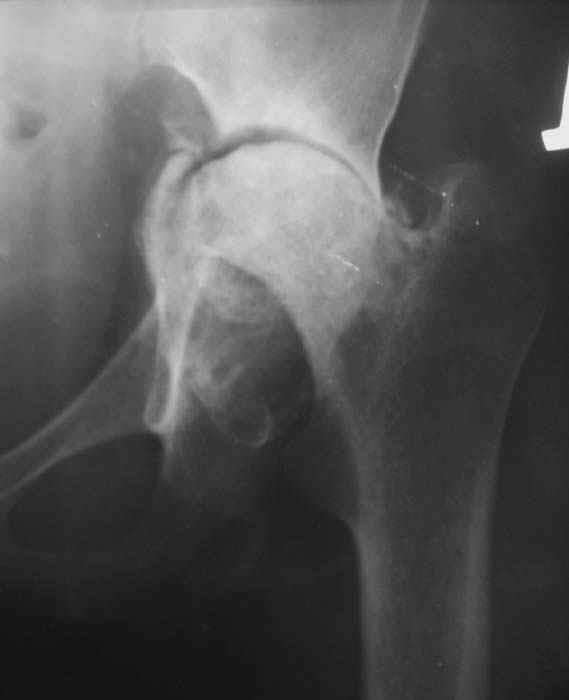

Уважаемые коллеги! Женщина, 28 лет. Страдает ревматоидным полиартритом, гормонозависима. 6 месяцев назад перенесла тотальное эндопротезирование левого тазобедренного сустава по поводу протрузионного коксита.

Использована цементная версия с пластикой дна впадины измельченной аутокостью и гранулами гидроксиапатита. Субъективное улучшение после операции. Улучшилось и стабилизировалось общее состояние. В настоящее время затруднено передвижение из-за поражения правого коленного сустава. Болезненный и <болтающийся> сустав. Предполагается замена сустава протезом без сохранения задней крестообразной связки. Возможные варианты? Заранее благодарю! С уважением, А.В.Владзимирский Донецкий НИИ травматологии и ортопедии Донецк, Украина